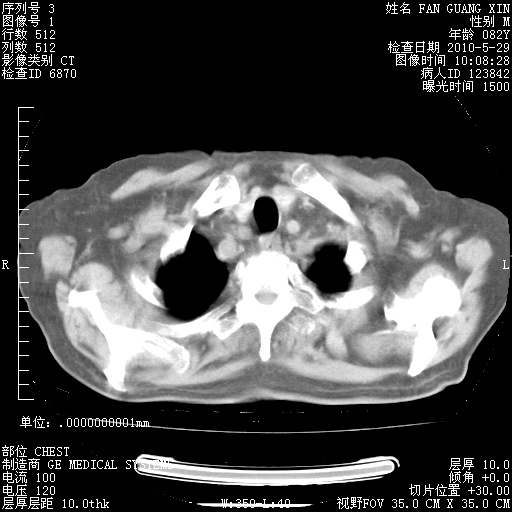

治疗3周后的肺部CT纵隔窗

再治疗10天后的肺部CT

再治疗10天后的肺部CT 纵膈窗

阅读此次胸部CT,肺间质渗出性改变较入院时有吸收。目前从体温、白细胞、中性分叶明显增高,肯定存在细菌感染(发生医院感染哦,若无消化道及泌尿系统等感染的依据,肺部感染可能大)。若你院头孢哌酮舒巴坦钠耐药率较高,同意你的方案,若48小时体温仍高,可考虑使用碳青霉稀类抗菌药物,同时可予超声雾化、注意滴数时加大液体量。白蛋白33.30g/L较低哦,需加强营养等支持治疗。